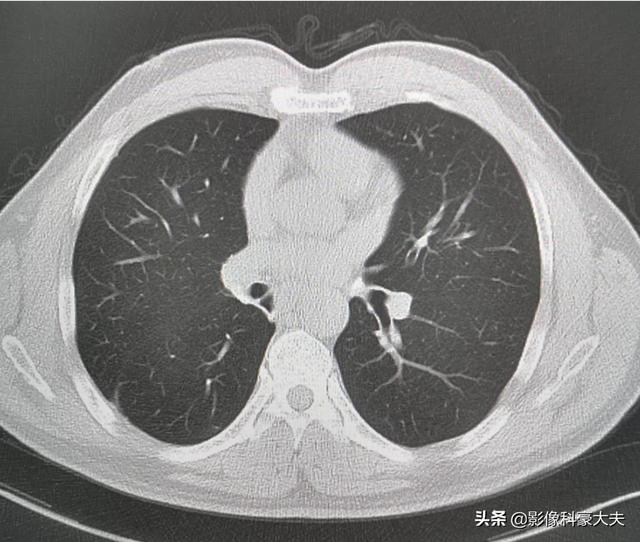

La récupération après une chirurgie du nodule pulmonaire est également liée au type de chirurgie pratiquée

La résection sous-lobaire (c'est-à-dire la résection segmentaire ou la résection en coin) a moins d'impact sur la fonction pulmonaire parce que moins de tissu pulmonaire est enlevé et qu'il reste plus de tissu pulmonaire normal. Si une lobectomie est pratiquée parce qu'une plus grande quantité de tissu pulmonaire est enlevée, il reste relativement moins de tissu pulmonaire normal, ce qui a un impact plus important sur la fonction pulmonaire et est plus susceptible de provoquer une gêne thoracique. Les photos suivantes montrent les poumons après deux résections différentes. La photo du haut montre la lobectomie du nodule pulmonaire inférieur droit, et vous pouvez voir que le poumon droit est significativement plus petit après l'opération. L'image du bas montre une résection sous-lobaire du nodule pulmonaire inférieur gauche, et vous pouvez voir que le poumon gauche conserve un volume plus important après l'opération.